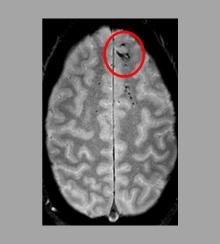

Microbleeds may worsen outcome after head injury National Institute of Neurological Disorders and Stroke

New technique makes brain scans better, MIT News

Aggressive Surgery Increases Survival with Low-Grade Brain Tumors

Elyse G.'s brain is fabulous. It's also missing a big chunk